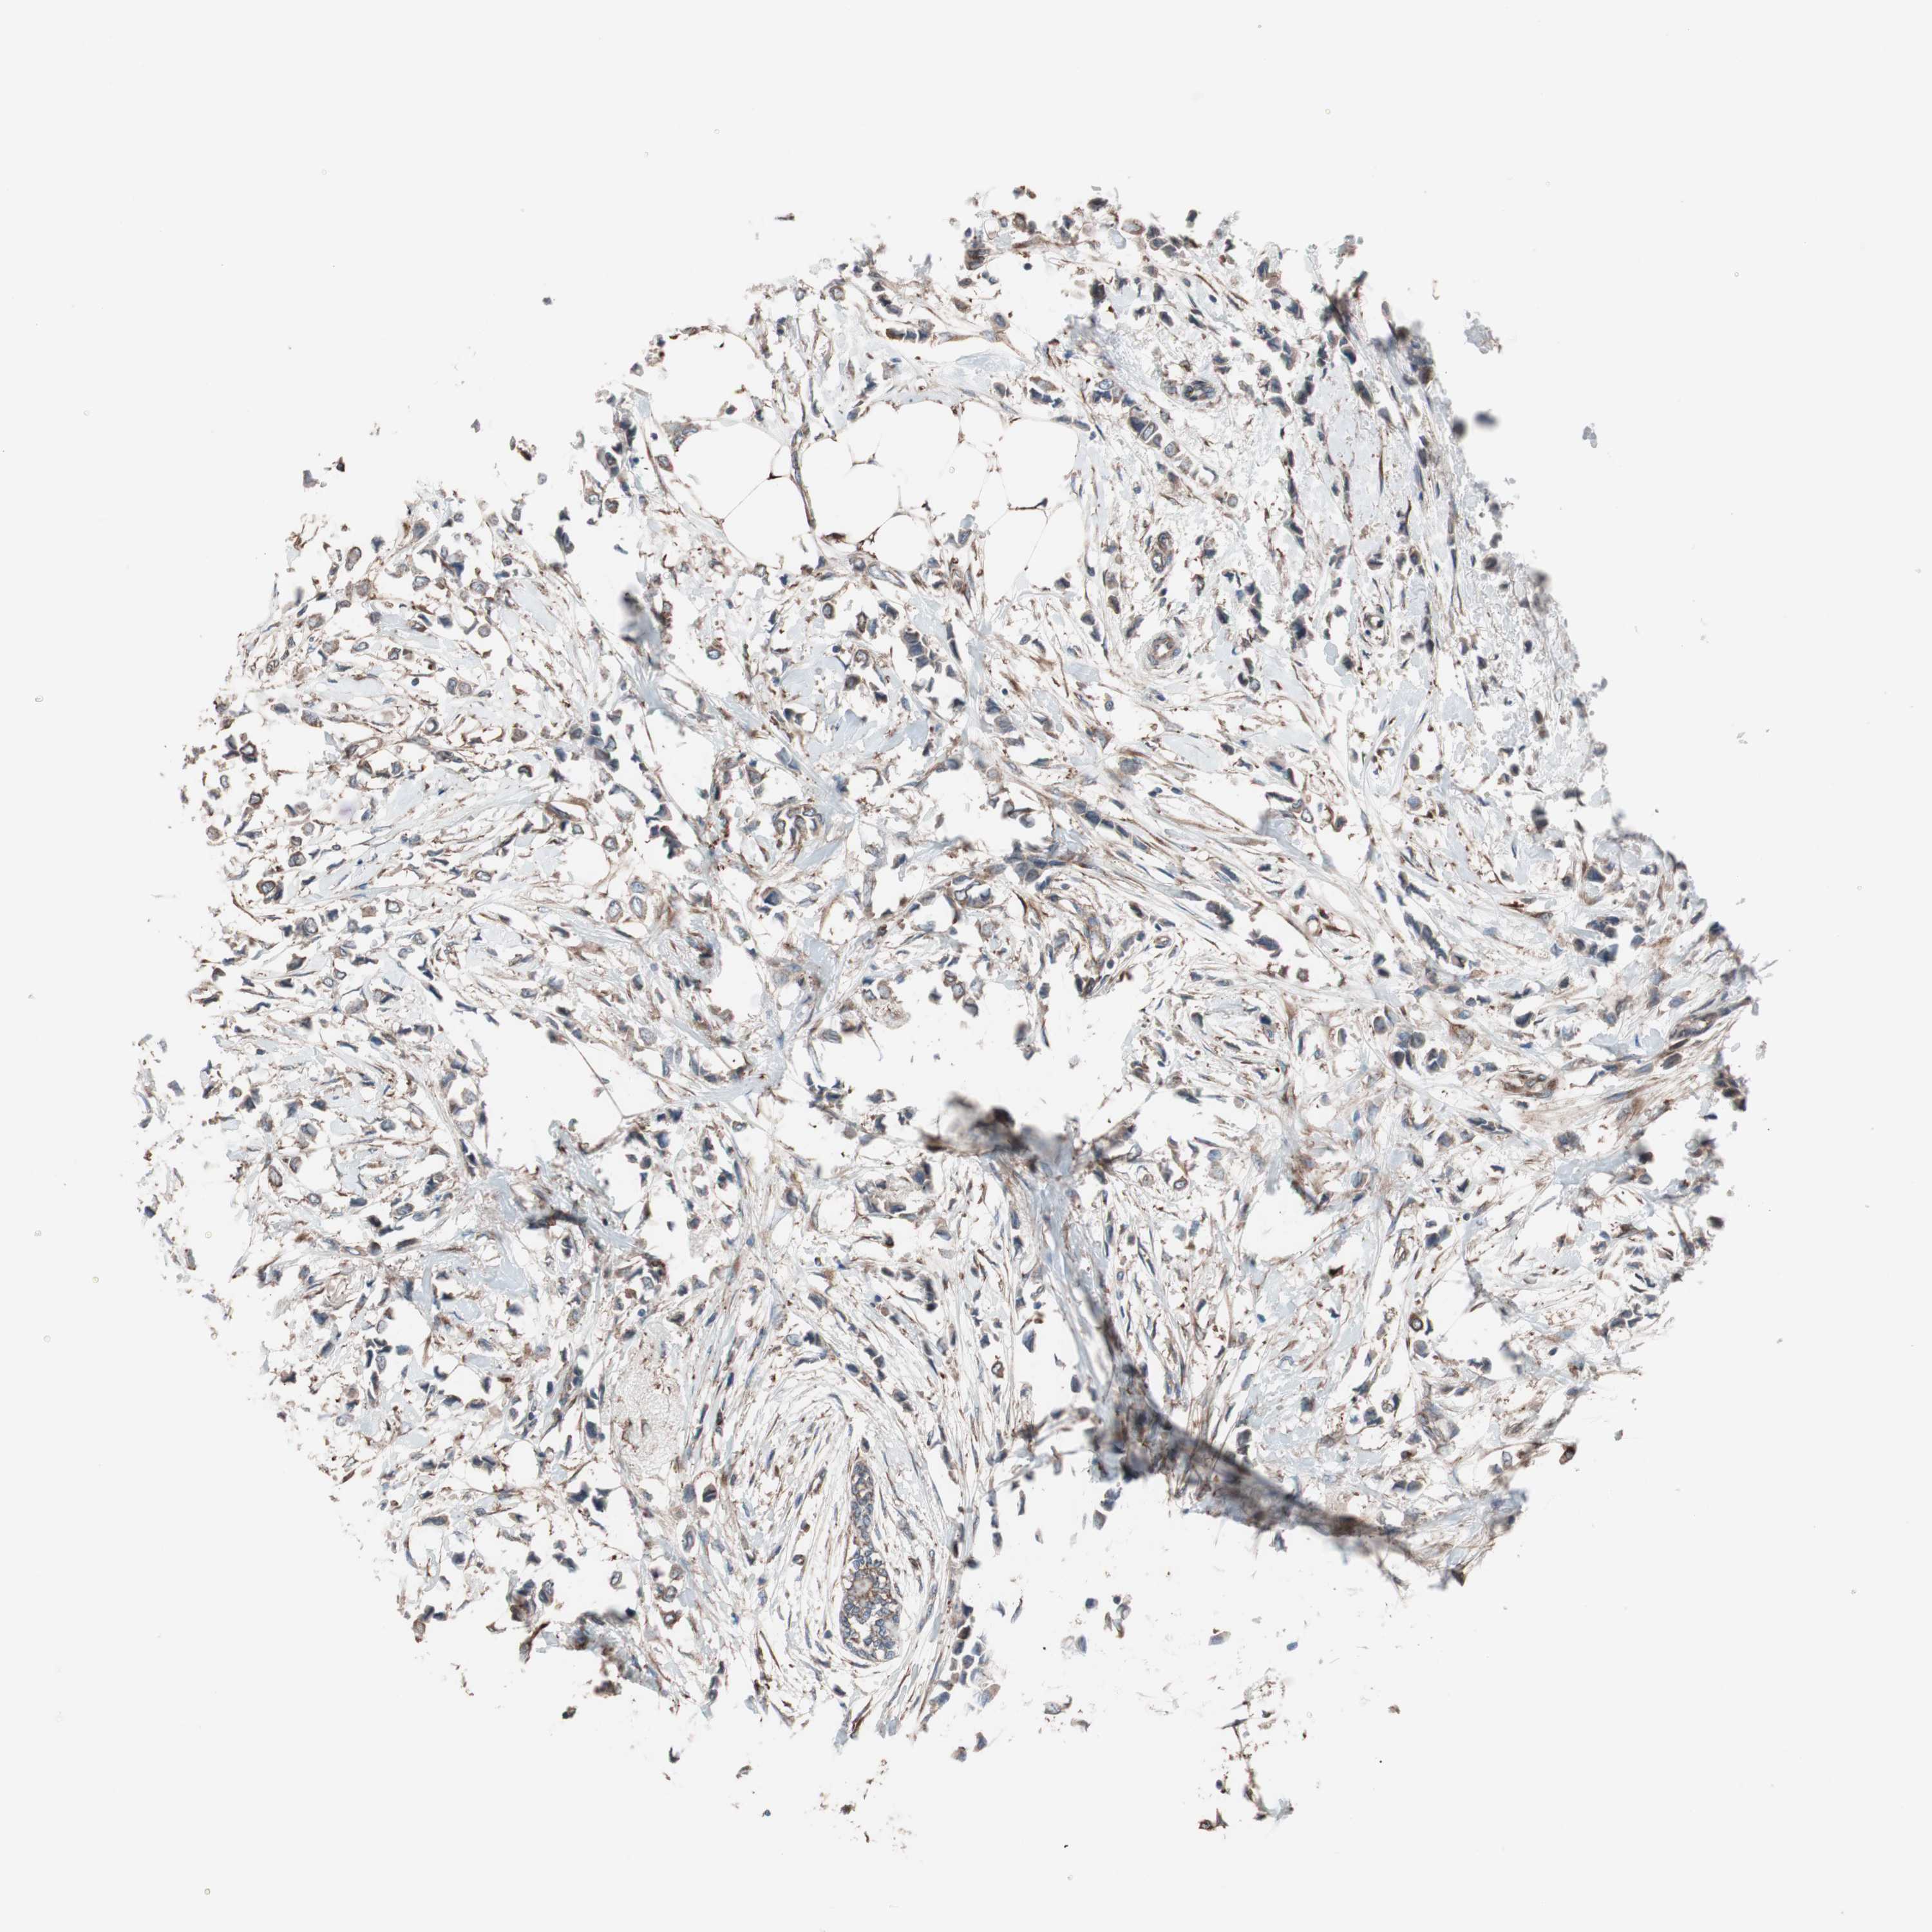

BRCA TCGA BRCA VALIDATION PROTEIN EXPRESSION

ANTIBODIES

AND

VALIDATION